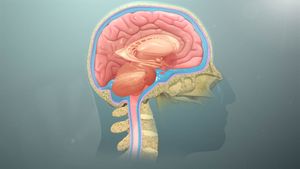

중추신경계는 뇌와 척수로 이루어진 신경계이다. 척주관은 척수를 포함하고, 두개강은 뇌를 포함한다. 중추신경계는 질긴 가죽과 같은 바깥층인 경막을 포함하는 3층 막 시스템인 수막에 의해 둘러싸여 보호된다. 뇌는 또한 두개골에 의해 보호되고 척수는 척추에 의해 보호된다.척추동물(인간 포함)의 신경계는 중추신경계(CNS)와 말초신경계(PNS)로 나뉜다. 중추신경계는 주요 분할이며, 뇌와 척수로 구성된다. 사람의 경우 특히 대뇌가 크게 발달해 있다.[47] 조직은 신경 조직이라고 불리며, 실제로 정보 전달을 수행하는 뉴런과 그 사이를 채우면서 수배나 존재하는 신경교세포 (글리아 세포)나 희소돌기아교세포, 별아교세포 등으로 구성된다.[48]

자율신경계는 주로 평활근의 운동과 분비샘의 활동을 지배하여 동물 내부 환경을 일정하게 유지하는 역할을 하는 신경계로, 교감신경과 부교감신경으로 이루어진다. 두 신경은 대부분 쌍으로 신체 기관과 연결되어 있어 서로 길항적인 작용을 한다. 자율신경계는 중추신경계 밖에서 뉴런을 한 번 교체한 후 말초에 이르며, 중추신경으로부터 자극을 전달받으면 교감신경은 노르에피네프린을, 부교감신경은 아세틸콜린을 분비한다. '자율신경'이라는 이름은 대뇌의 직접적인 지배를 받지 않는다는 의미로 붙여졌으나, 실제로는 시상하부를 비롯한 여러 중추신경의 지배를 받아 어느 정도 의식적인 조절이 가능하다.[54]말초신경계(PNS)는 체성 신경계와 자율신경계로 나뉜다. 자율신경계(내장 신경계)는 내부 장기, 혈관, 분비샘을 지배하는 뉴런으로 구성되며, 교감 신경계와 부교감 신경계로 다시 나뉜다.